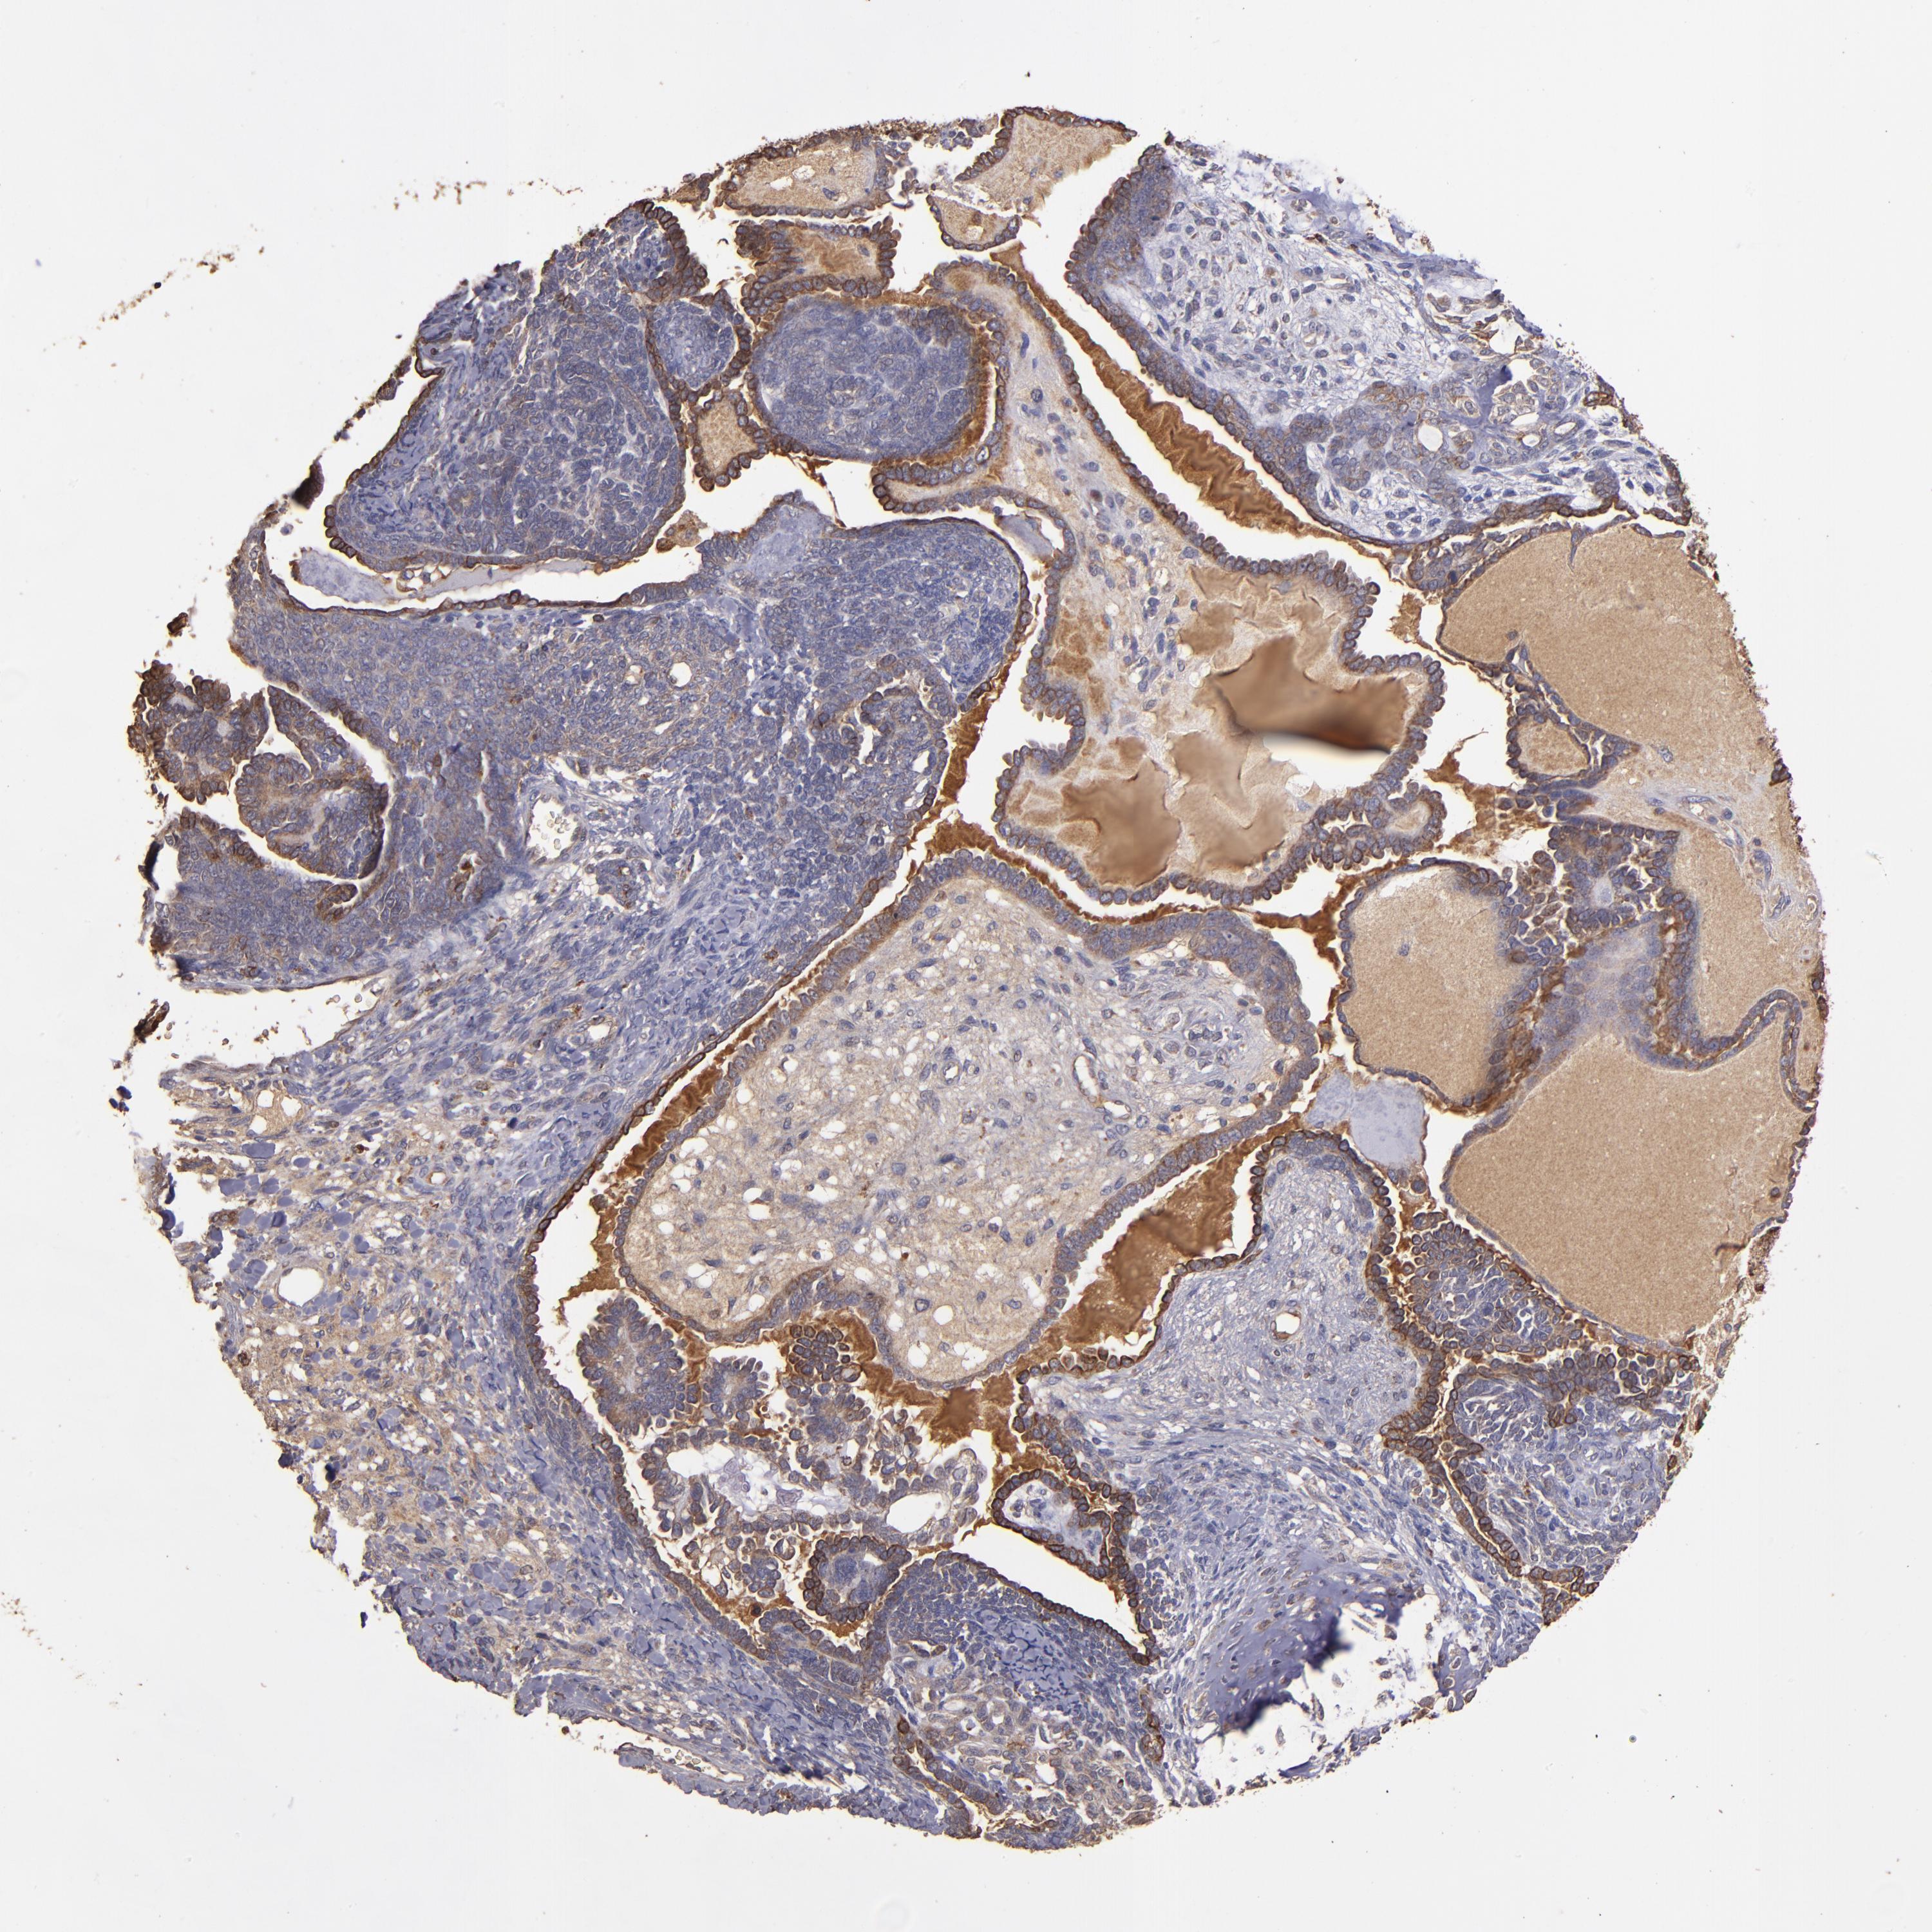

ENDOMETRIAL CANCER - Protein expressioni

A mouse-over function shows sample information and annotation data. Click on an image to view it in a full screen mode. Samples can be filtered based on level of antibody staining by selecting one or several of the following categories: high, medium, low and not detected. The assay and annotation is described here.

Note that samples used for immunohistochemistry by the Human Protein Atlas do not correspond to samples in the TCGA dataset.

Antibody stainingi

Antibody staining in the annotated cell types in the current human tissue is reported as not detected, low, medium, or high, based on conventional immunohistochemistry profiling in selected tissues. This score is based on the combination of the staining intensity and fraction of stained cells.

Each image is clickable and will lead to virtual microscopy that enables deeper exploration of all samples and also displays staining intensity scores, fraction scores and subcellular localization as well as patient and tissue information for each sample.

Antibody HPA002945

Staining

High

Medium

Low

Not detected

Intensity

Strong

Moderate

Weak

Negative

Quantity

>75%

75%-25%

<25%

None

Location

Nuclear

Cytoplasmic/membranous

Cytoplasmic/membranous,nuclear

Adenocarcinoma, NOS

Neoplasm, malignant, NOS